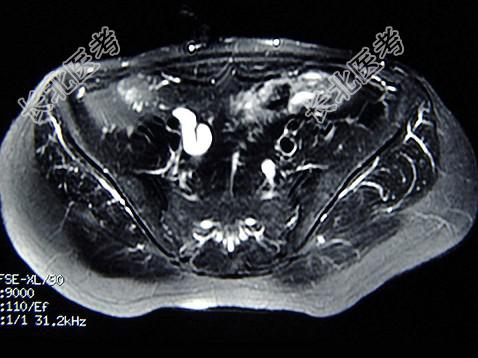

多项选择题女,31岁, 右侧腰部胀痛不适,MRI检查如图所示, 下列说法正确的是 ( )

A、右肾重度积水

B、右侧输尿管粗细不均并迂曲扩张

C、右侧输尿管下段呈囊样扩张

D、左肾输尿管未见异常

E、考虑为右侧输尿管囊肿